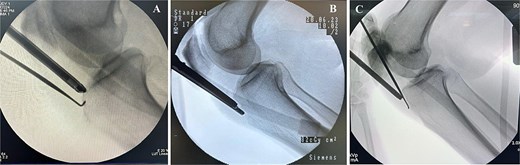

Preoperative MRI was used to determine the mediolateral position of the ossicles, using the femoral condyles as landmark relative to the tibial ossicles. Fluoroscopic guidance was also used intraoperatively to identify the level of the tibial ossicle in a lateral X-ray (Fig. 3) with the help of an 18 gauge spinal needle (Fig. 4).

Intraoperative fluoroscopy views show ossicle before excision and complete removal. (A) Case 1. (B) Case 2. (C) Case 3, marking the position of the ossicle using arthroscopic spinal needle.